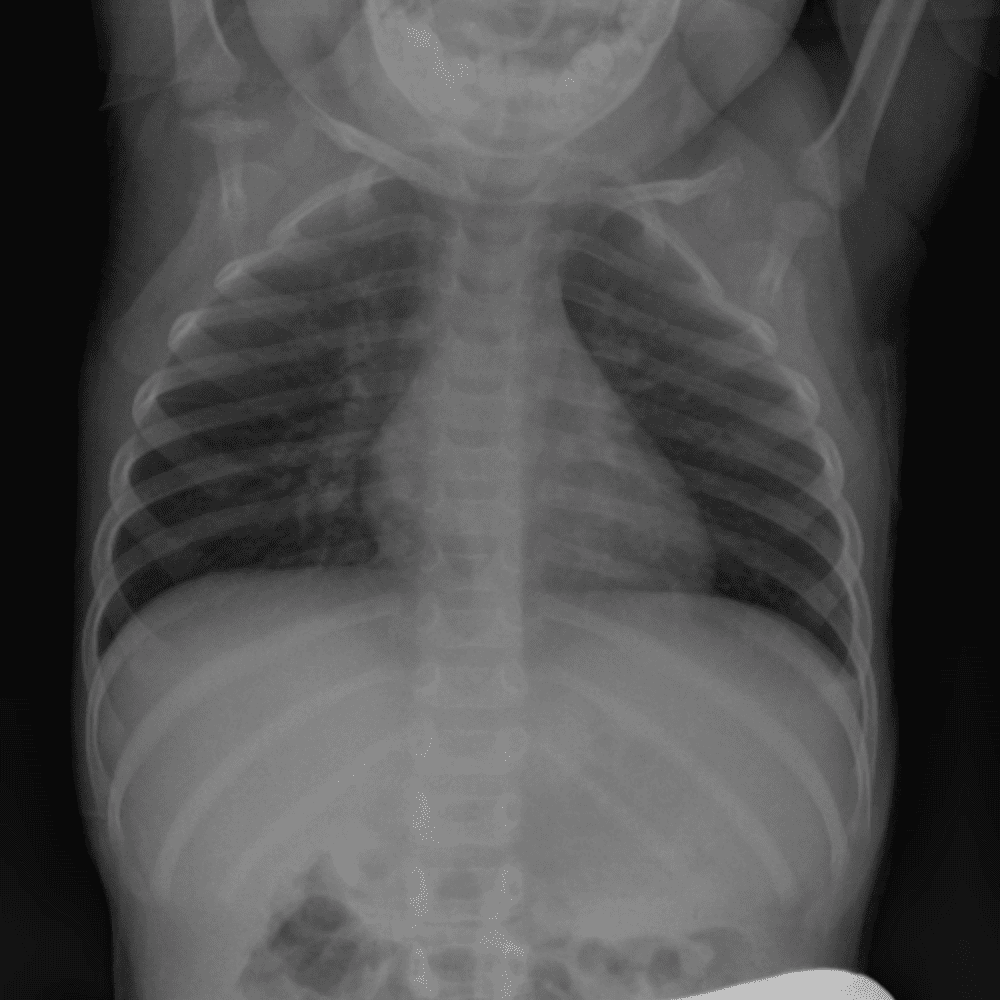

Peds Chest

Practice

Simulates call by including subtle or difficult cases and some normals.

50 cases